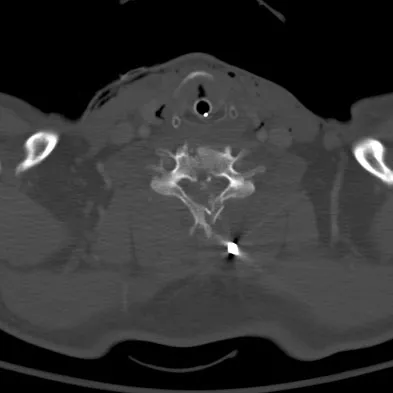

A 47-year-old woman has had a 1-month history of left hip and medial thigh pain that is exacerbated by sitting. Laboratory studies show a total protein level of 8.2 g/dL (normal 6.0 to 8.0) and an immunoglobulin G (IGG) level of 2,130 mg/dL (normal 562 to 1,835). A radiograph, CT scan, and biopsy specimen are shown in Figures 38a through 38c. What is the most likely diagnosis?

Explanation

The laboratory studies and histology are both consistent with myeloma. Infection should show white blood cells other than plasma cells on histology. Lymphoma would show lymphocytes, not plasma cells. The lack of bone formation on the imaging studies and the lack of osteoid on histology rule out osteosarcoma. The cells have too much cytoplasm and nuclear chromatin to be Ewing's sarcoma cells.